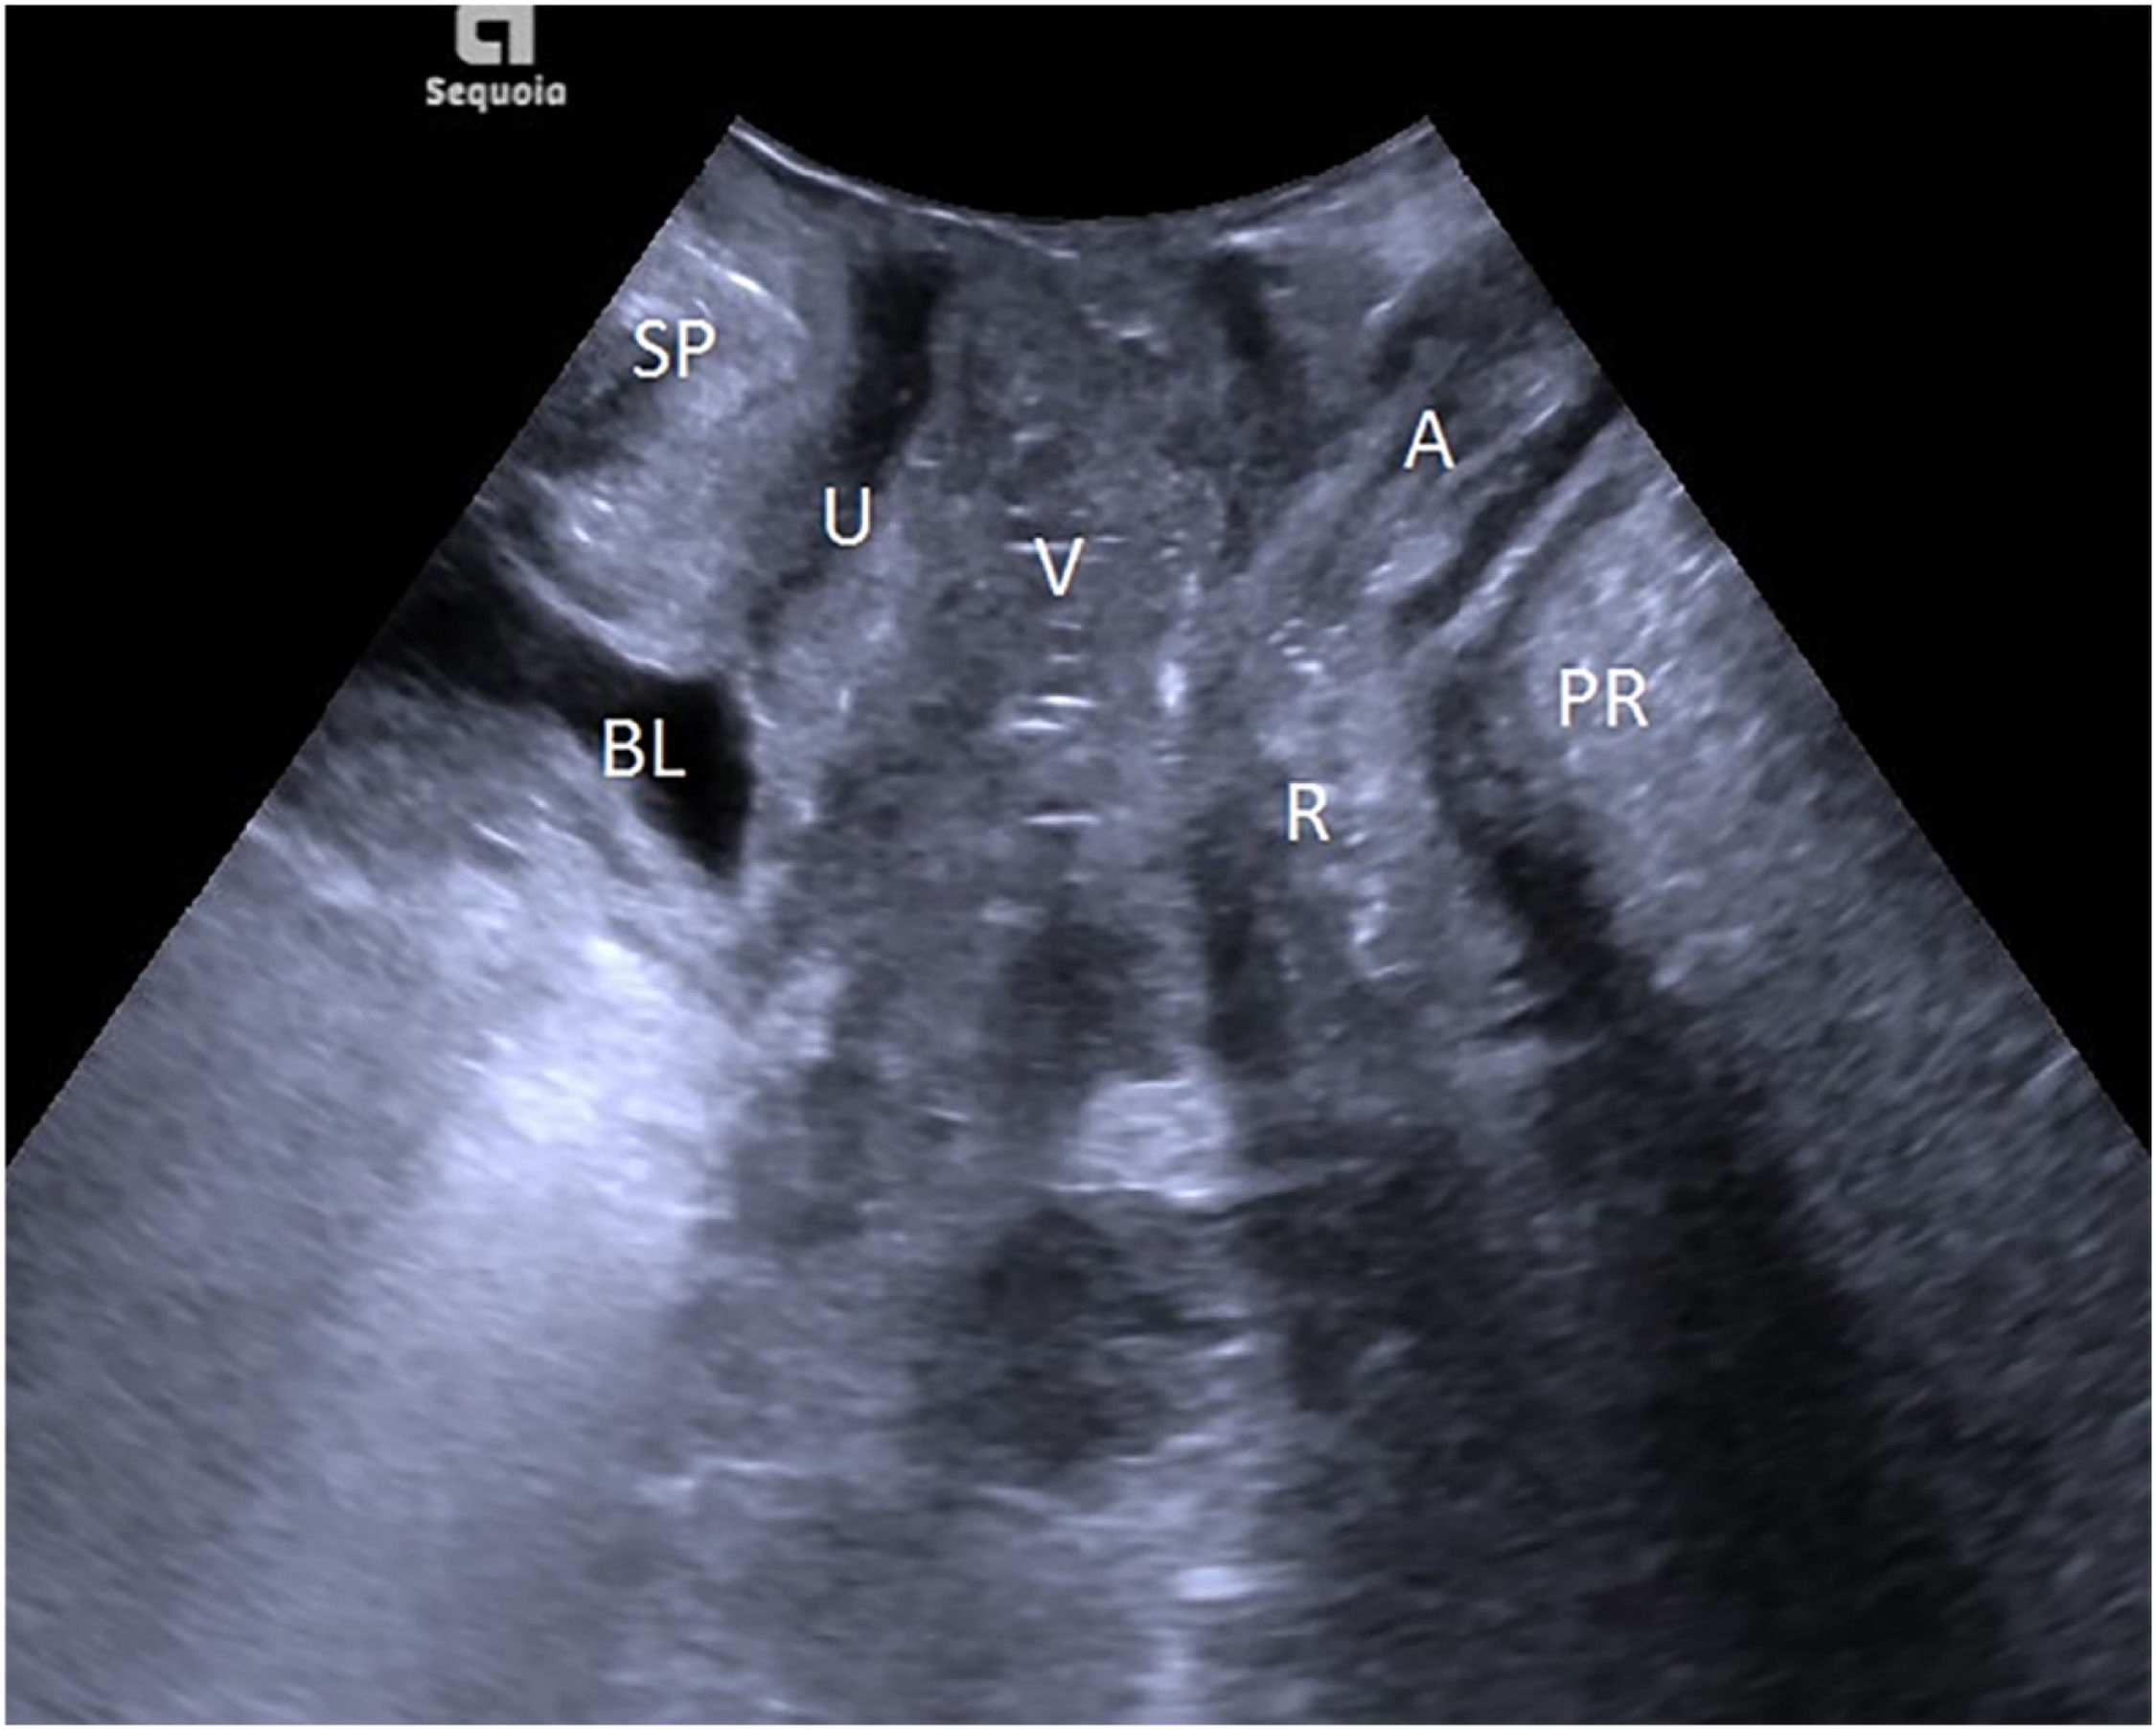

TPUS examinationThe patient emptied her bladder with a residual urine volume of less than or equal to 50 mL before the TPUS examination and then took a lithotomy position. The probe was protected with a disposable condom and placed vertically in the center of the perineum to determine a median sagittal plane. From the ventral side to the dorsal side, sequential display of the Symphysis Pubis (SP), urethra, bladder, vagina, anorectal junction, and the central part of the levator plate was performed, as shown in Fig. 1. The horizontal line running across the posterior lower margin of SP was taken as the reference line, and the alterations in the movements of pelvic floor organs and tissues at rest and at maximal Valsalva maneuver, and levator ani contraction were observed, their respective distances from the reference line were measured, and three times of measurement were conducted to determine the lowest point. The states of resting, maximal Valsalva, and levator ani contraction were denoted with the respective letters R, V, and C. Related parameters: Bladder Neck-Symphyseal Distance (BSD), Anorectal Junction-Symphyseal Distance (ASD), with positive values above the line and negative values below the line; Posterior Urethravesical Angle (PUA), and Urethral Obliquity Angle (UOA), as shown in Figure S1. A previous study indicated that the UOA was not statistically significant and thus discarded,9 and the Urethral Rotation Angle (URA) derived from UOA was adopted, which is the difference in UOA between resting and maximum Valsalve states; the Bladder Neck Descent (BND) is a difference in BSD between resting and maximum Valsalve states; the Anteroposterior Diameter of the Hiatus (HAPD) is the distance between SP and the medial margin of the levator plate, as shown in Figure S2. Effective Valsalva maneuvers (increasing abdominal pressure to push the pelvic organs to the caudal side) lasted for 6S, and the levator ani contraction lasted for 3S.